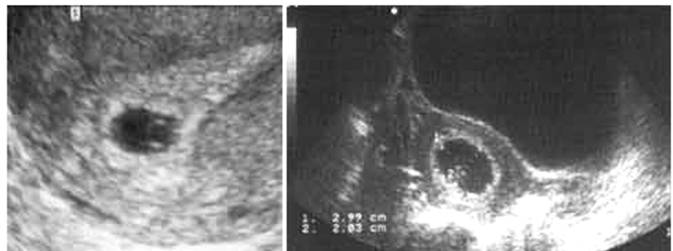

Échographie pelvienne, au mieux par voie vaginale. Dans une grossesse normale, le sac ovulaire est visible dès 5 Semaines d'Aménorrhée (SA) sous la forme d'une image liquidienne intra-utérine entourée d'une couronne échogène (le trophoblaste